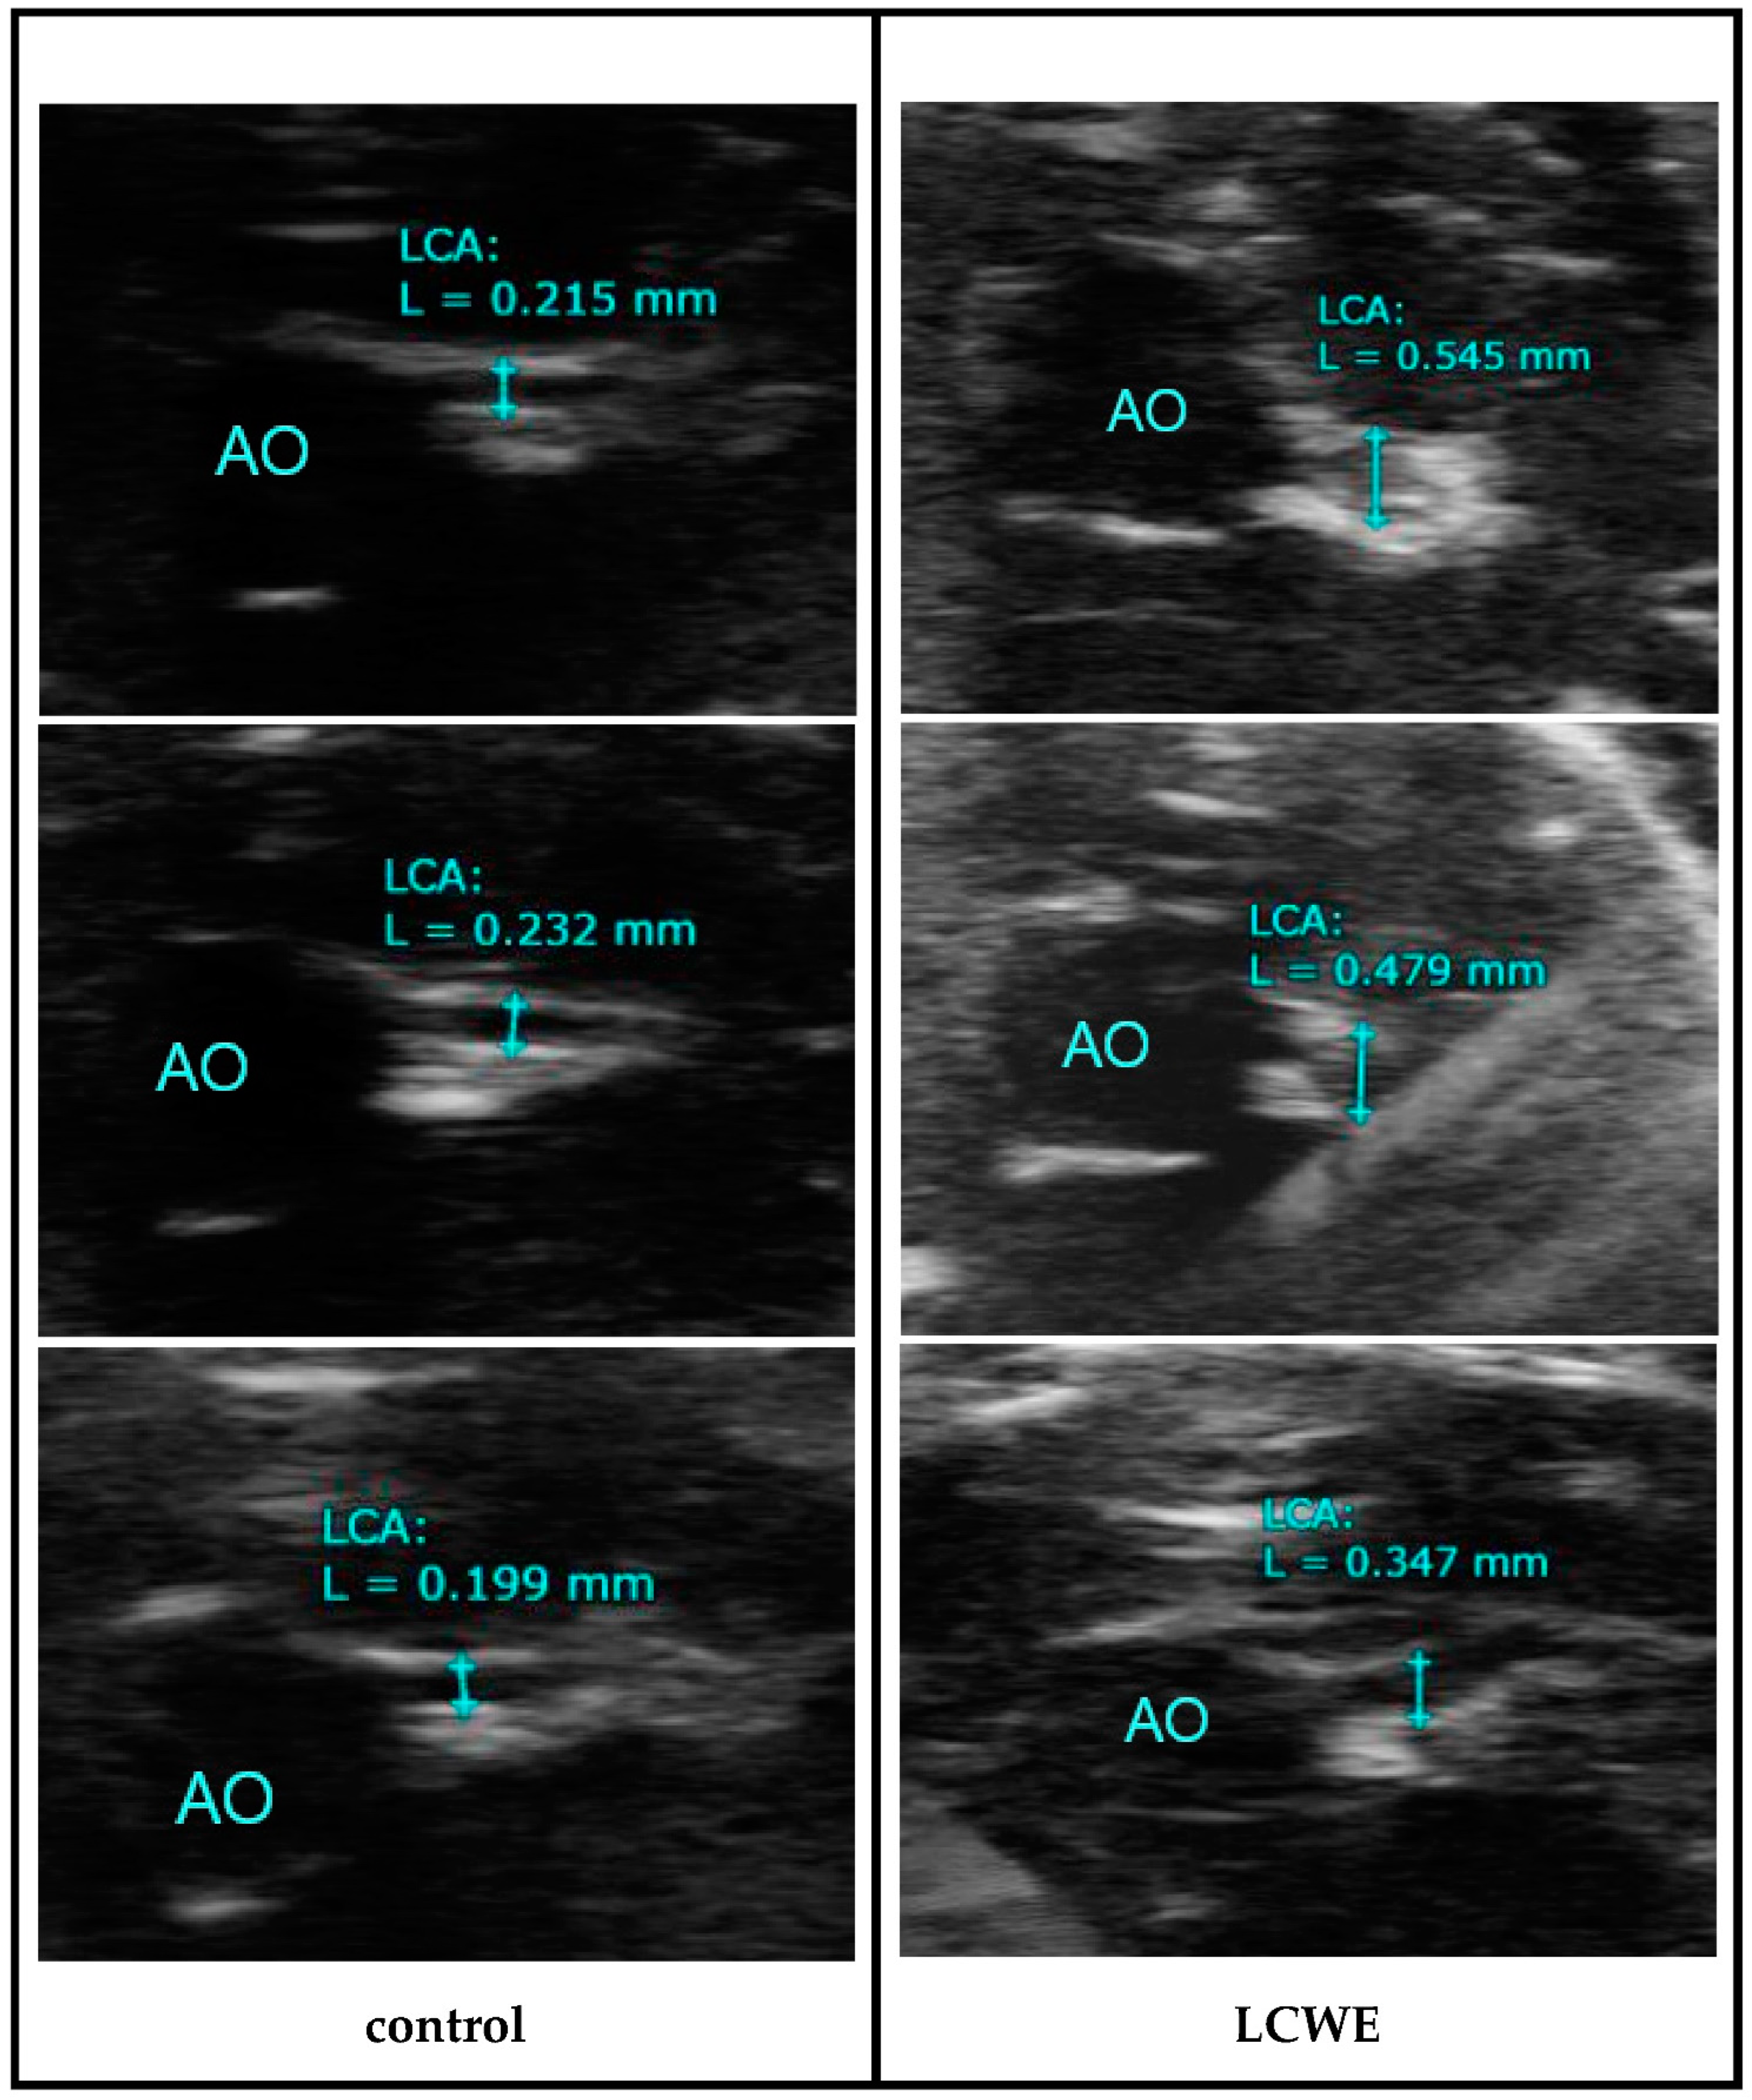

The flowchart of this study is presented in Figure 1, illustrating the key components such as the animals involved, the timeline of the study, and the echography procedures. As shown in Figure 2, echocardiography of the LCWE group’s (intraperitoneal injection 2 mg/kg for 7 days) coronary artery diameter on day 28 after study was significantly greater than that of the control group (no LCWE treatment). The normal range of coronary artery diameter was found to be 0.217 ± 0.028 mm (N = 18), while the outer coronary artery diameter was 0.472 ± 0.056 mm (N = 37). Sonography of carotid artery wall thickness in the LCWE group on day 28 after the study showed a significant increase compared to the control group (Figure 3). Carotid artery wall thickness significantly increased in the LCWE group with the narrowing of the internal diameter when compared with the control group.

Figure 2.

Coronary artery diameter in the control group (no treatment) and LCWE group (intraperitoneal injection 2 mg/kg for 7 days) by echocardiography on day 28 after study (AO: aorta, LCA: left main coronary artery, L: diameter).